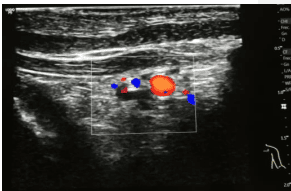

En aquellos casos de mayor complejidad en los que podamos dudar de la canalización accidental del vaso arterial podemos realizar una visualización en plano transversal. Este plano nos permitirá visualizar un punto hiperecogénico correspondiente a la guía metálica en el interior de la luz del vaso canalizado. De manera habitual podemos encontrar la imagen de la guía reposada en la zona inferior de la luz del vaso.

En las siguientes imágenes podemos observar la guía metálica en el interior de la luz del vaso izquierdo y posterior identificación del vaso arterial en la zona axilar mediante el uso del Doppler color. Esta simple comprobación nos permite asegurar la correcta canalización del vaso venoso con datos objetivos.

Mediante estas comprobaciones podemos confirmar el correcto desarrollo de la técnica de canalización para, posteriormente, proceder a la dilatación del punto de inserción y su trayecto, mediante la inserción del microintroductor con cánula pelable a través de la guía, en el interior de la luz del vaso con la máxima seguridad.